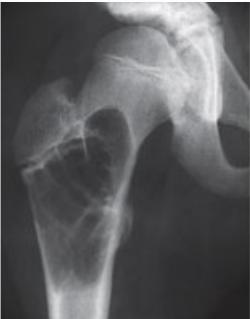

Clinical Example

- 11 year old boy: Pain in left hip

Osteoid Osteoma

- Small tumor (<1 cm)

- Young adults

- Pain, pain, pain:

- Typically relieved by Salicylates

- Sites: Femur, tibia, spine

- X-ray:

- Small radiolucent “nidus”

- Surrounded by sclerotic bone

- CT: Shows “nidus” better

- scan: hot

- Treatment: surgical excision, or thermal ablation